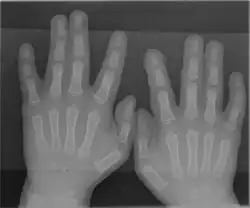

![]() The fingers of a left hand seen from both sides | |